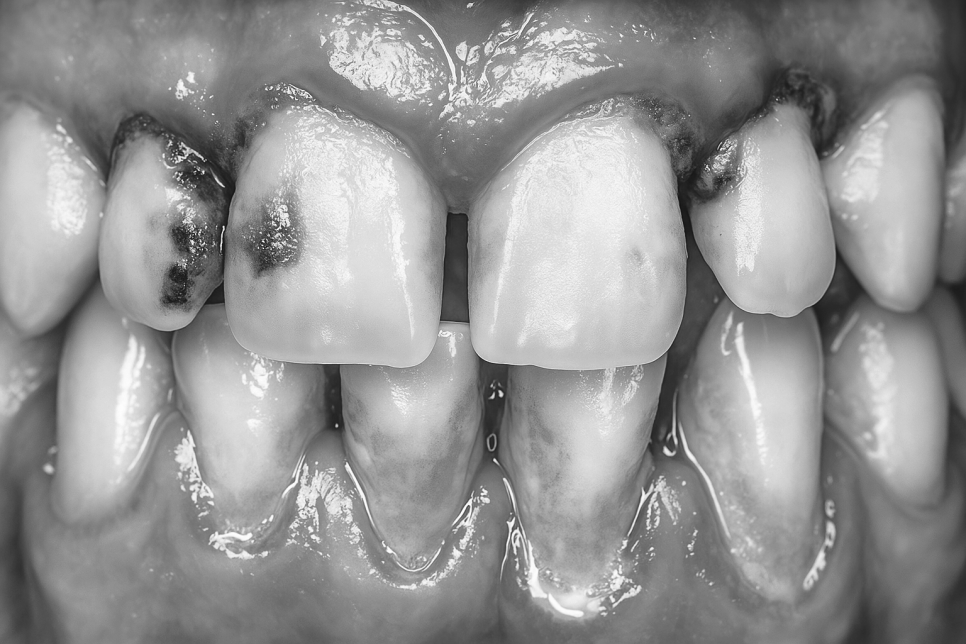

치은염(Gingivitis)은 치은에 생기는

염증성 질환으로 주로 치아 표면에 쌓인

플라그(치태)라는 세균막이 쌓이며 발병합니다.

붉게 부어 오르거나 양치를 할 대

치실을 사용할 때 피가 나는 것은

그 초기 증세랍니다.

치아를 지지하는 조직과 치조골에

염증이 생겨 점차 조직과 뼈가

파괴되는 예후를 보이는 만성 치주염은

초기엔 그저 붓고 출혈이 일어나는

치은염 단계에서 출발하나

이를 방치했을 때 염증이

치조골까지 번져 파괴하고

치아 고정력을 저하시키게 됩니다.